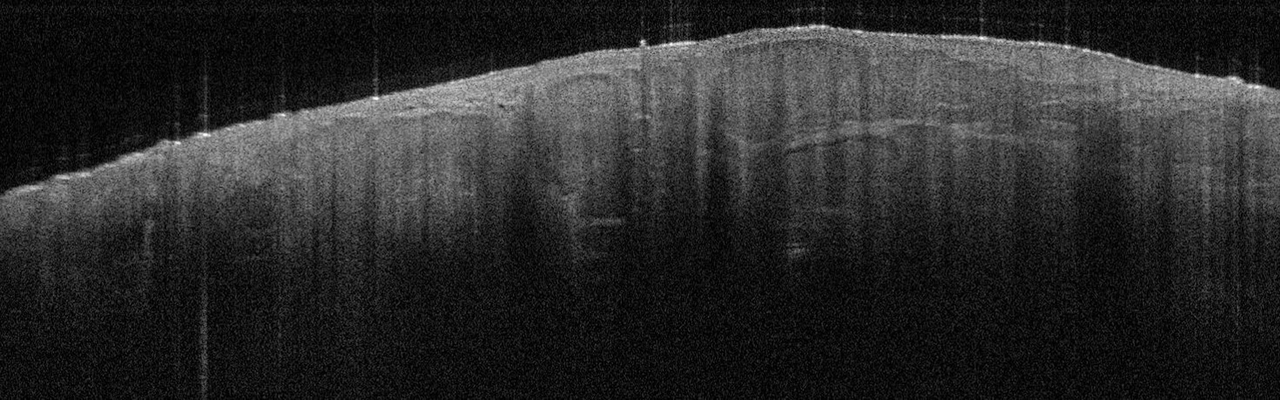

Die Tumorzellverbände des BCC erkennt man in der Aufnahme als signalarme, ovoide Nester mit dunk­lem Randsaum, die von hellem Stroma umgeben sind. Die Epidermis ist abgeflacht, Teleangiektasien kann man als kleine dunkle Löcher sehen. Eine aktinische Keratose sieht anders aus: In diesem Fall sind Hornschicht und Epidermis verdickt, oft sieht man auch weiße Streifen in der Hornschicht, so die Referentin. In Abgrenzung zum Plattenepithelkarzinom erscheint die dermoepidermale Junktion bei der aktinitischen Keratose intakt. Beim Plattenepithelkarzinom werden zudem helle Bereiche deutlich, bei denen es sich um Hornzysten handelt.

Das superfizielle BCC ist charakterisiert durch die oberflächlichen Tumornester, die wie Perlen an einer Kette aufgereiht von der Epidermis in die darunterliegende Dermis ragen. Das superfizielle BCC ist charakterisiert durch die oberflächlichen Tumornester, die wie Perlen an einer Kette aufgereiht von der Epidermis in die darunterliegende Dermis ragen. © Prof. Dr. Julia Welzel